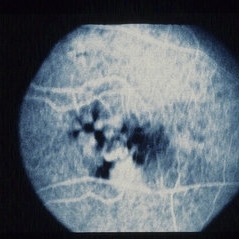

Proliferative Diabetic Retinopathy (PDR)

Sep 11 2012 by Hamid Ahmadieh, MD

FA image of a 55-year-old woman with active PDR.

Photographer: Hamid Ahmadieh, MD, Ophthalmic Research Center, Labbafinejad Medical Center, Shahid Beheshti University of Medical Sciences

Imaging device: Heidelberg HRA

Condition/keywords: preretinal hemorrhage, retinal neovascularization